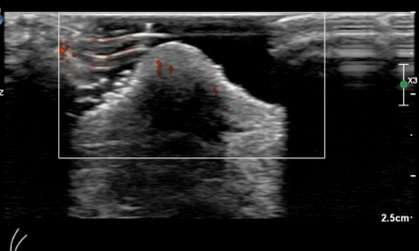

Case: Paget's Disease Figure 2

Figure 2: Targeted ultrasound of the left nipple shows increased vascularity but without a discrete mass.